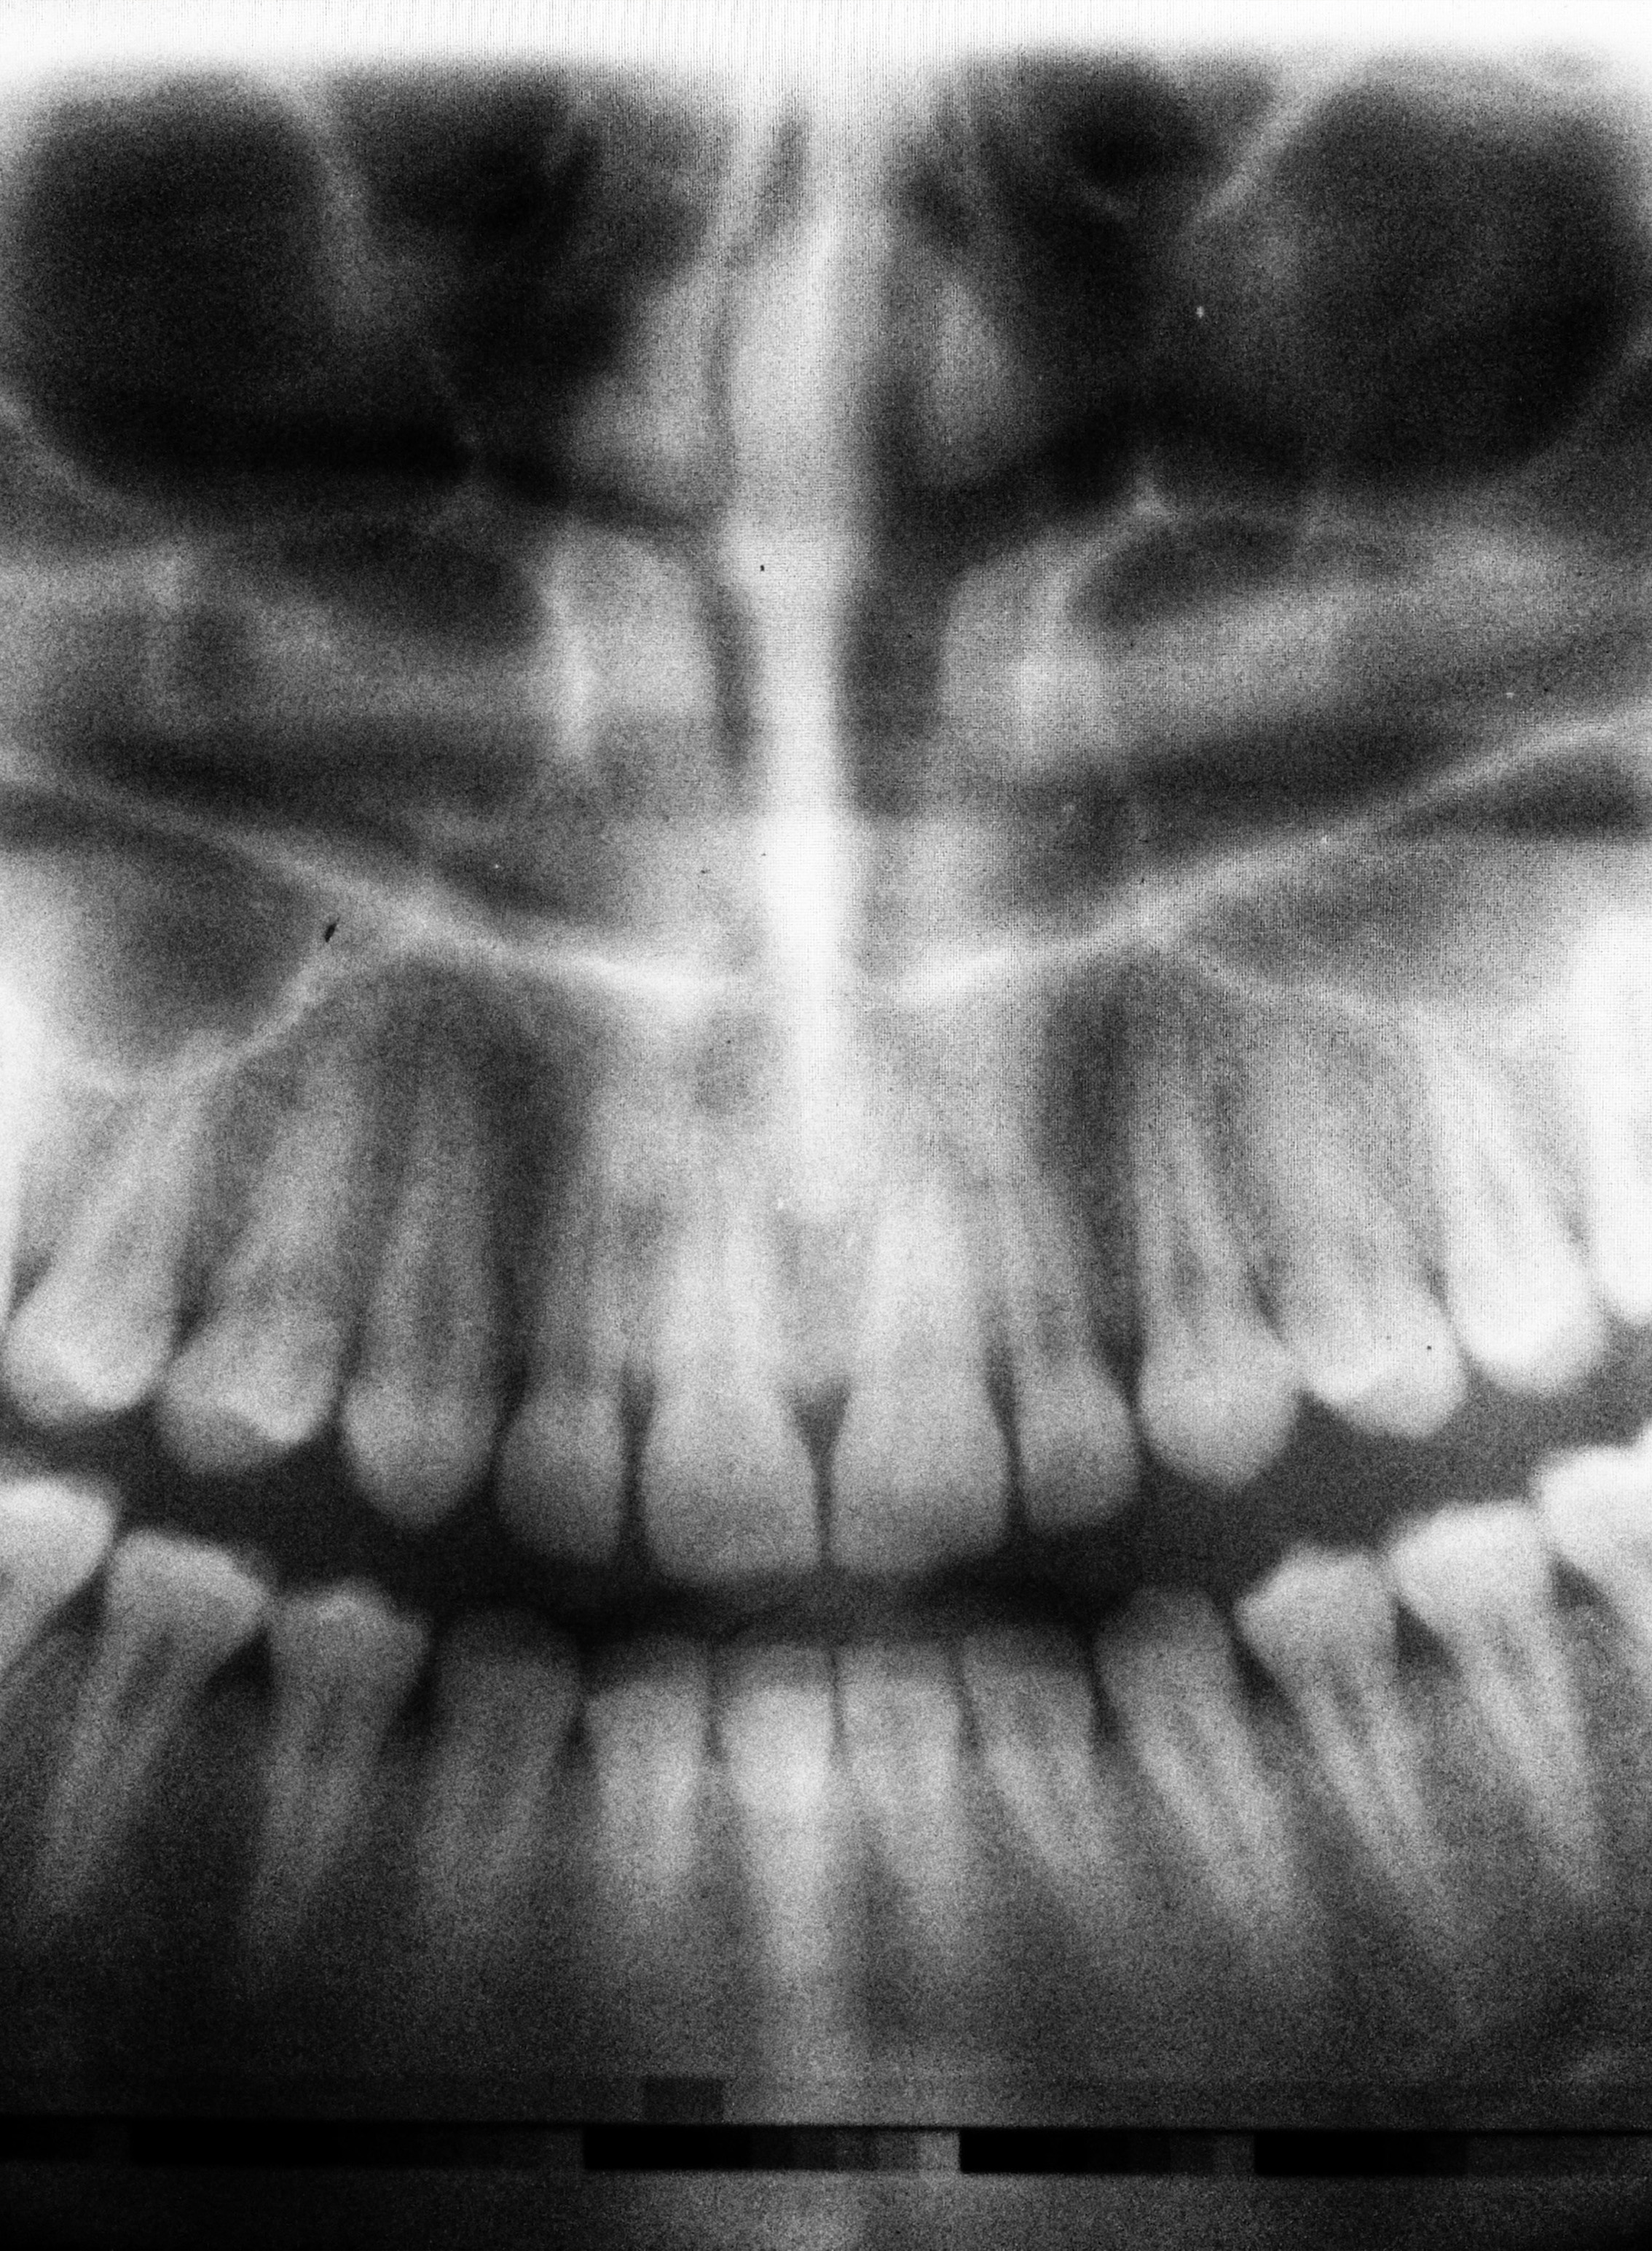

Quando parliamo di odontoiatria conservativa ci riferiamo ad una particolare branca della medicina odontoiatrico-restaurativa, branca che si occupa in specifico della cura degli elementi dentali aggrediti da lesioni cariose, mediante rimozione della stessa e successiva occlusione delle cavità risultanti dalla inevitabile asportazione di parti di smalto e dentina.

Nel caso di carie superficiali, l'odontoiatria conservativa adotta metodi il meno possibile invasivi, asportando solo quelle parti di dente interessato al danno. Purtroppo nei casi di carie profonde, che interessano cioè la polpa dentaria e i nervi, si rende necessaria la completa devitalizzazione dei canali radicolari.

Le carie infatti possono intaccare tutte le parti dell'elemento dentale, compromettendolo su tutti i lati. Attraverso la medicina conservativa i medici specializzati possono garantire al paziente la risoluzione di problemi gravi, nonché un rimedio ai dolori insopportabili che seguono il corso degenerativo di una carie.